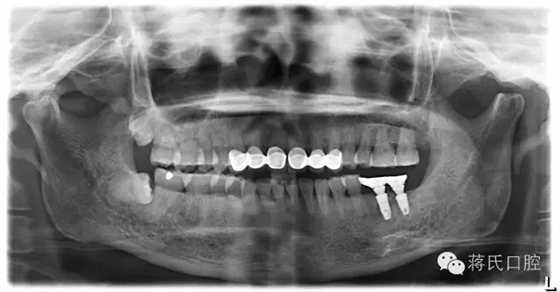

4.修復(fù)后正面,咬合距離低以純鈦冠修復(fù),植體角度良好所以連冠修復(fù)

5.修復(fù)后咬合

6.修復(fù)后全景片